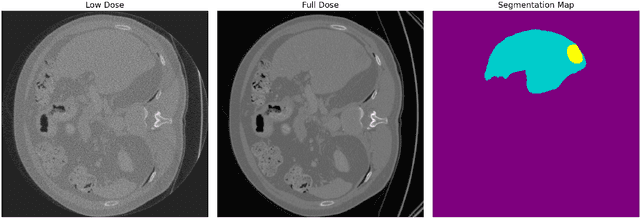

Deep learning-based low-dose computed tomography reconstruction methods already achieve high performance on standard image quality metrics like peak signal-to-noise ratio and structural similarity index measure. Yet, they frequently fail to preserve the critical anatomical details needed for diagnostic tasks. This fundamental limitation hinders their clinical applicability despite their high metric scores. We propose a novel task-adaptive reconstruction framework that addresses this gap by incorporating a frozen pre-trained task network as a regularization term in the reconstruction loss function. Unlike existing joint-training approaches that simultaneously optimize both reconstruction and task networks, and risk diverging from satisfactory reconstructions, our method leverages a pre-trained task model to guide reconstruction training while still maintaining diagnostic quality. We validate our framework on a liver and liver tumor segmentation task. Our task-adaptive models achieve Dice scores up to 0.707, approaching the performance of full-dose scans (0.874), and substantially outperforming joint-training approaches (0.331) and traditional reconstruction methods (0.626). Critically, our framework can be integrated into any existing deep learning-based reconstruction model through simple loss function modification, enabling widespread adoption for task-adaptive optimization in clinical practice. Our codes are available at: https://github.com/itu-biai/task_adaptive_ct